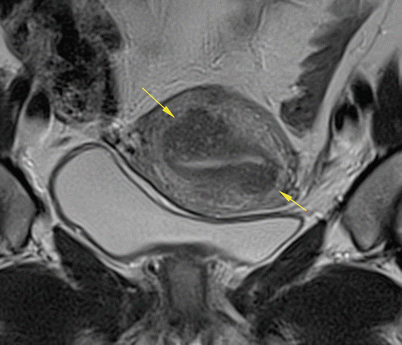

Fig. 7.9

Coronal oblique, TSE, T2 weighting. Apart from the thickening and heterogeneity of the myometrium, endometrial striations, which are adenomyosis characteristics, can also be identified (arrows). A small myoma (arrowhead) and volumetric increase can be identified as well